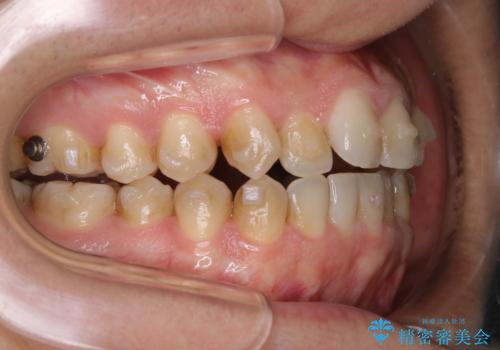

インビザラインで矯正治療中のクリーニング(PMTC)

- 全体的にクリーニングしてほしいとのことで来院されました。

PMTC60分コースを行いました。

インビザラインでの矯正治療は、歯の表面にアタッチメントといって白い突起を付けますので、材料の質的にも普段よりも汚れがかなり付着します。着色も付きやすいです。

虫歯や歯周病が進行しないように定期的にクリーニングすることをおすすめします。インビザライン経過のチェックが2、3ヶ月に1回のためそのくらいのペースで一緒にクリーニング行うことが最適です。